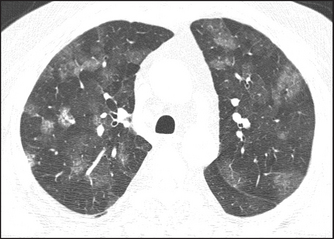

High-resolution CT scans give more detailed information about the lungs but expose the patient to hundreds of times more radiation. They are particularly useful for diagnosing interstitial lung disease, pulmonary haemorrhage (see Figure 12.13) and bronchiectasis (see Figure 12.14). Primary and secondary lung tumours are best imaged with CT and tuberculous involvement of the lungs can be quantified (see Figure 12.15).

Figure 12.13 Pulmonary haemorrhage (From Hansell D. Imaging of diseases of the chest, 5th edn. Mosby, 2009.)